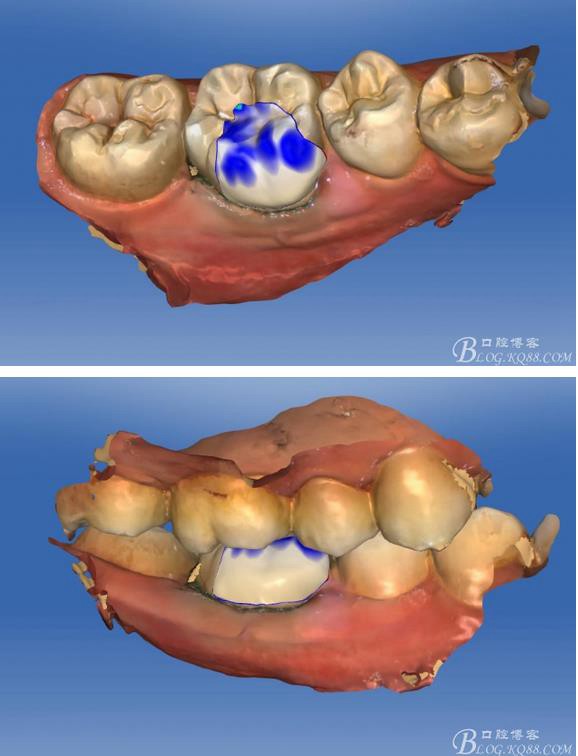

畫(huà)線(xiàn)是最關(guān)鍵的,線(xiàn)畫(huà)不好制出的修復(fù)體會(huì)出現(xiàn)邊緣缺損 或多 或少,醫(yī)生和技術(shù)配合

掃描 畫(huà)線(xiàn) 準(zhǔn)備研磨